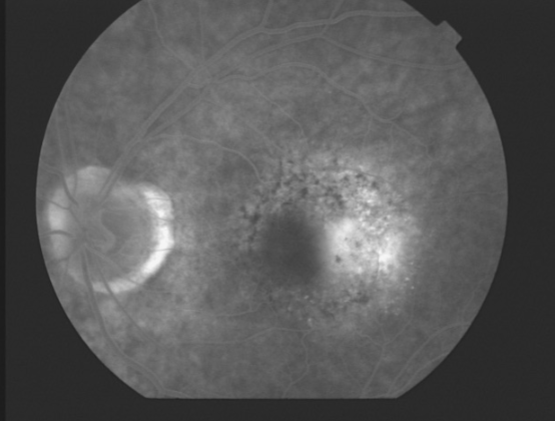

CNV

ingrowth of new vessels extending from the choroid into sub-RPE space in one or more areas

neovascular buds invade & penetrate the degenerated Bruch’s membrane & proliferate beneath the RPE

occult stage/Gass type 1

initial blood flow is very slow through CNVM

fibrovascular PED or late leakage of underdetermined source

breaks through Bruch’s but staying sub-RPE

classic CNV/Gass type 2

CNVM

well defined hyperfluorescence

cartwheel or sea fan appearance

thought to break through RPE & staying sub-retinal

type 1 MNV

fibrovascular PED

late leakage from undetermined source (poorly defined neovascularization)

speckled hyperfluorescence

dye pooling late in study

poorly defined

classic CNV

classic & occult CNV